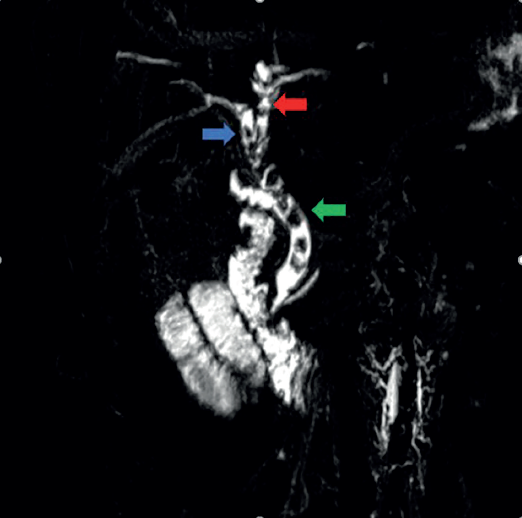

Paciente del sexo masculino, de 36 años, sin an tecedentes de importancia. Inició su cuadro con cólico vesicular, irradiación hacia espalda y hombro derecho y náuseas. A la exploración se observó tinte ictérico, dolor a la palpación media y profunda en el hipocondrio derecho y epigastrio. No cuenta con estudios de laboratorio. Se sospechó coledocolitiasis y se realizó una colangioresonancia que confirmó el diagnóstico (figura 2).

Figura 2 Colangioresonancia en reconstrucción 3D coronal en donde se identifican múltiples imágenes con ausencia de señal en relación con litos y dilatación de vía biliar intra y extra hepática, conducto hepático derecho (flecha azul), conducto hepático izquierdo (flecha roja), conducto colédoco (flecha verde).